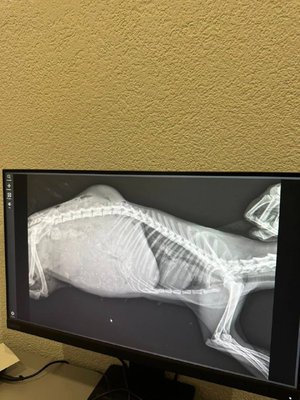

Після звернення адміністрації навчального закладу рятувальники тварин одразу прибули на місце. Тварину доставили до ветеринарної клініки, де зробили рентген. Саме тоді з’ясувалося, що єнотовидна собака чекає на потомство.

“Стан майбутньої мами - критичний. Зараз ми боремося не просто за одне життя, а за цілу сім’ю”, - зазначили зоозахисники.

Зараз тварина перебуває під наглядом ветеринарів.